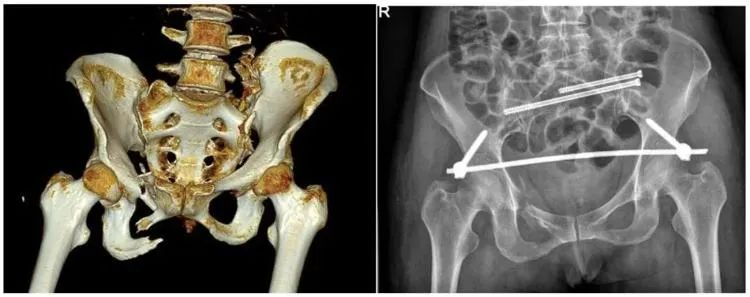

【医疗科普】:不稳定性骨折影像

不稳定性骨折

【医疗科普】:大尺寸平板C形臂提供更多图像细节

普爱医疗推出的大平板一体式C形臂PLX119C,配置30cm×30cm平板探测器,大视野,能够呈现更多图像细节,对于诸如骨盆双侧骨折类型手术或骨盆后环内固定术具有应用优势,一次曝光可获取全部骨折部位影像,可简化曝光流程,提高手术效率。